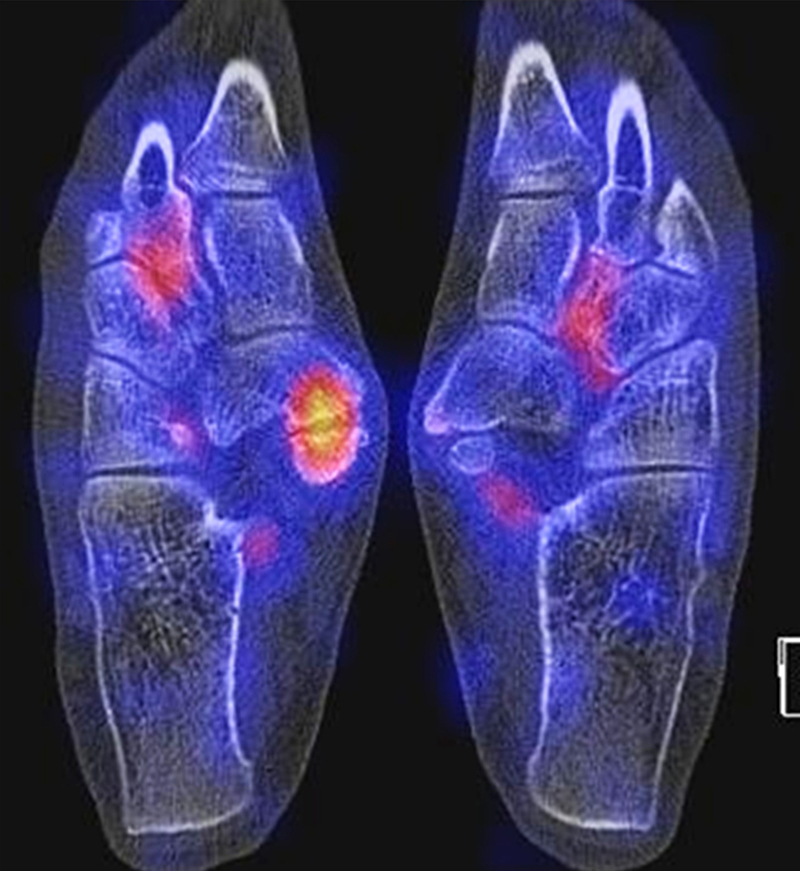

Abbildung 9.4.a bis d: SPECT/CT bei V. a. TMT-2-Arthrose rechts. Anamnestisch seit ca. 12 Wochen extreme Schmerzen im rechten Fuß, begleitend lokale Schwellung. Zuvor in der Pflege tätig mit vermehrter körperlicher Belastung, seit dem Wechsel in eine überwiegende sitzende Tätigkeit tendenzielle Besserung der Beschwerden. Kein auslösendes Ereignis erinnerlich. Hausärztlicherseits wurde eine Hyperurikämie ausgeschlossen. Körpergewicht 124 kg. Szintigraphisch ist die rechte Fußwurzel in allen 3 Phasen szintigraphisch anreichernd bzw. positiv. Die ersten beiden Phasen weisen auf die Hyperämie hin. Im CT erkennt man im Seitenvergleich eine diffuse regionale Osteopenie mit verwaschener Knochenstruktur und punctum maximum im Os naviculare und Os cuneiforme intermedius. Der linke Fuß zum Vergleich ist unauffällig.